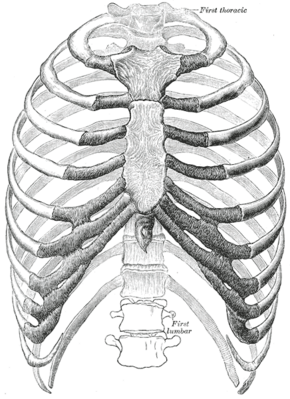

![]() Detail of a single human rib | |

The parts of a rib includes the head, neck, body (or shaft), tubercle, and angle.

The head of the rib lies next to a vertebra. The ribs connect to the vertebrae with two costovertebral joints, one on the head and one on the neck. The head of the rib has a superior and an inferior articulating region, separated by a crest. These articulate with the superior and inferior costal facets on the connecting vertebrae.[5] The crest gives attachment to the intra-articulate ligament that joins the rib to the vertebra of the same number, at the intervertebral disc. Another ligament, the radiate ligament joins the head of the rib to both the body of the upper vertebra and to the body of the lower vertebra. The smaller middle part of the ligament connects to the intervertebral disc. This plane joint is known as the articulation of the head of the rib.

The other costovertebral joint is that between the tubercle on the neck and the transverse process of the joining thoracic vertebra of the same rib number, and this is known as the costotransverse joint. The superior costotransverse ligament attaches from the non-articular facet of the tubercle to the transverse process of the vertebra.

The neck of the rib is a flattened part that extends laterally from the head. The neck is about 3 cm long. Its anterior surface is flat and smooth, whilst its posterior is perforated by numerous foramina and its surface rough, to give attachment to the ligament of the neck. Its upper border presents a rough crest (crista colli costae) for the attachment of the anterior costotransverse ligament; its lower border is rounded.

A tubercle of rib on the posterior surface of the neck of the rib, has two facets (surfaces) one articulating and one non-articulating. The articular facet, is small and oval and is the lower and more medial of the two, and connects to the transverse costal facet on the thoracic vertebra of the same rib number.[5] The transverse costal facet is on the end of the transverse process of the lower of the two vertebrae to which the head is connected. The non-articular portion is a rough elevation and affords attachment to the ligament of the tubercle. The tubercle is much more prominent in the upper ribs than in the lower ribs.